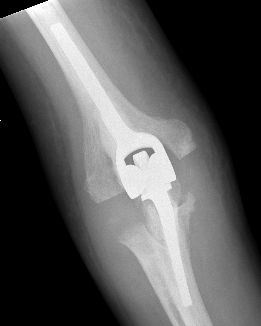

Coonrad-Morrey Discovery Elbow Latitude

Technique Total Elbow Arthroplasty

Vumedi video Coonrad-Morrey approach and prosthesis

Arthroplasty

5. Insert cement restrictors / implant ulna and humeral prosthesis

7. Link components

8. Repair collaterals if needed